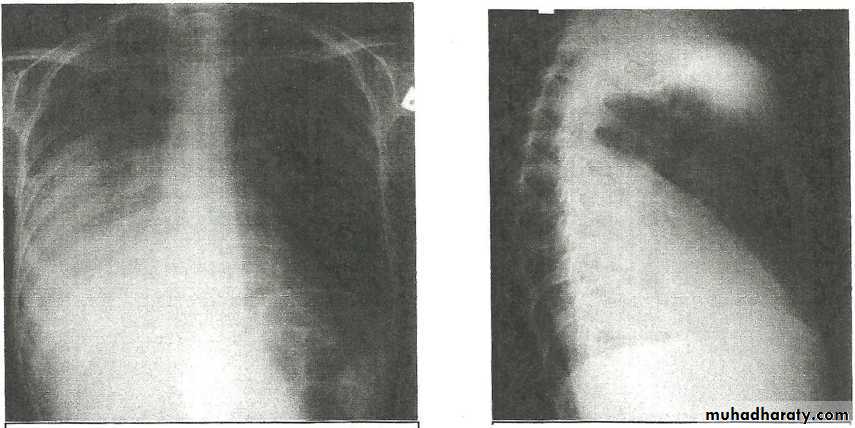

The plain film shows features which are typical for spinal tuberculous disease.

There is an extensive paraspinal soft-tissue mass.

Detail in the underlying spine is poor but there is early crowding of ribs posteriorly, indicating early vertebral collapse.

(B) Coronal MR image of the thoracic spine demonstrates destruction of the intervertebral disc at the point where the paraspinal widening is maximal and this change is associated with alteration of signal from the vertebrae.